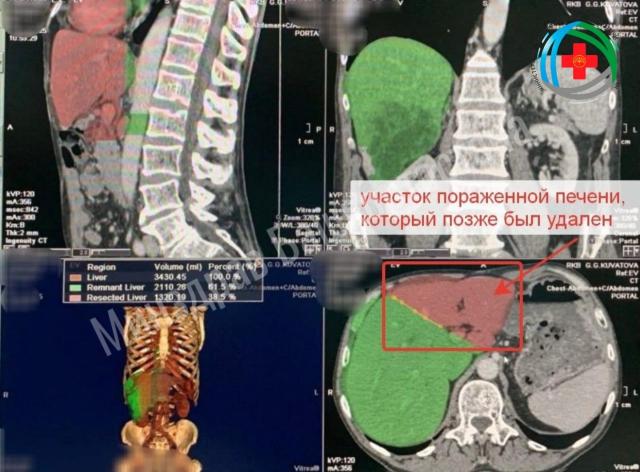

Врачи в Башкирии «нарастили» пациенту новую печень